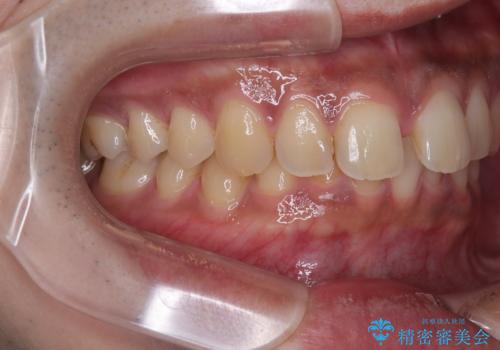

- 上の前歯の正中離開(すきっ歯)と、下顎前歯部の叢生(デコボコ)を主訴に来院された患者様の症例です。

「目立ちにくい装置で治療したい」とのご希望があり、透明のマウスピース矯正であるインビザラインを用いて矯正治療を行いました。